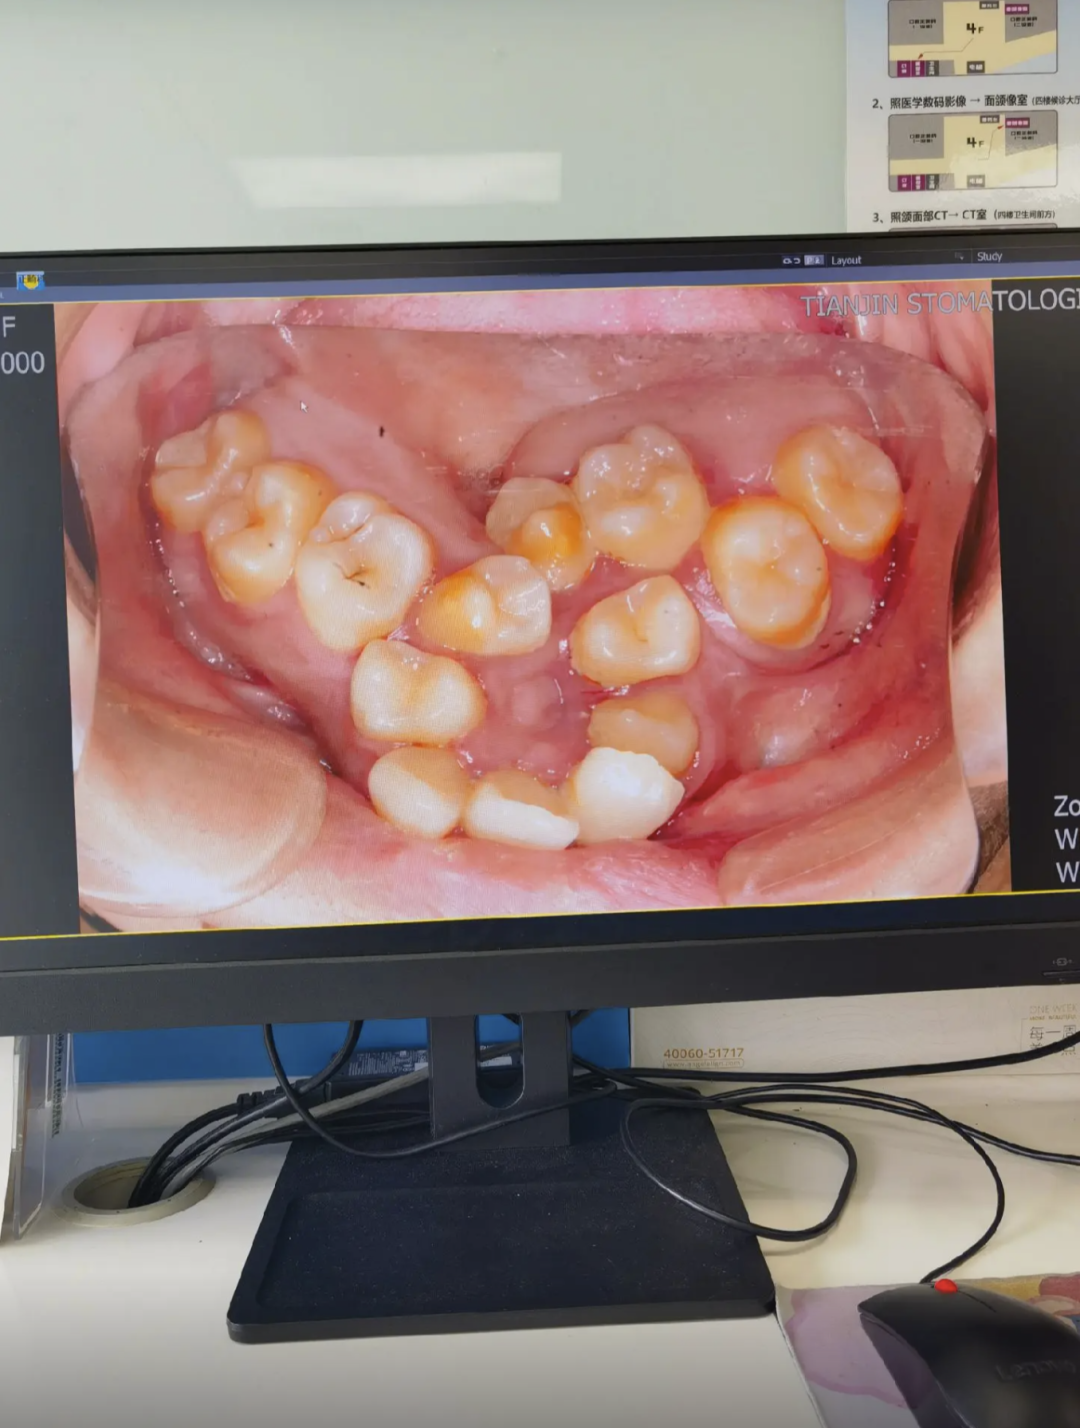

上图这种智齿很艰难的萌出,因为空间不足明显顶着第二恒磨牙长,这会引发第二恒磨牙的健康出现问题,并因为中间存在空隙导致容易堆积食物残渣难以清洁到位引发蛀牙问题等,甚至冠周炎都有一个专门的分类叫智齿冠周炎。

但不要觉得上图这种智齿是很严重的,相反那是最轻的,好歹都算萌出了,没办法萌出的智齿一大堆,甚至因为空间不足导致横着长的都有,生长目标十分明确的对准第二恒磨牙的牙根,不把宝贵的第二恒磨牙顶死誓不罢休。